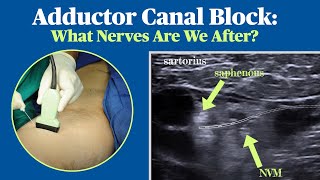

ACL Block #3 - Adductor Canal Catheter Adductor Canal Block: What Nerves Are We After?

Adductor Canal Block: What Nerves Are We After? Adductor Canal Block

ACL Block #3 - Adductor Canal Catheter Adductor Canal Block: What Nerves Are We After?

Adductor Canal Block: What Nerves Are We After? Adductor Canal Block